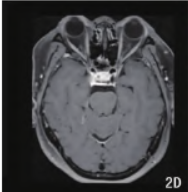

实验室检查:患者术前ACTH明显高于正常值,并处于波动升高状态,最高>440.40pmol/L。另外其催乳素35.96ng/mL,明显高于参考值范围(4.79~23.3ng/mL)。患者行常规磁共振检查显示垂体上缘平坦,垂体柄居中,未见明显异常信号灶及强化灶(图1)。

1.png

图1患者术前常规磁共振检查垂体未见明显异常